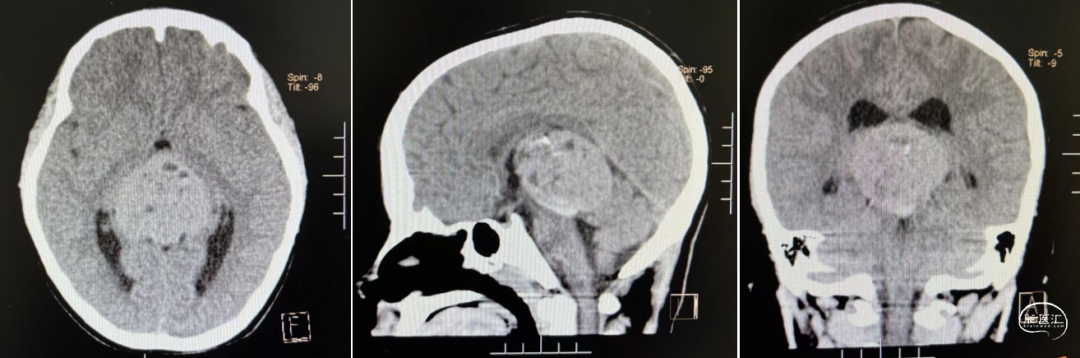

头部CT显示:鞍区-鞍上区-双侧额叶-胼胝体前份可见一不规则形囊实性肿块,实性部分密度稍高,平扫CT值约39HU,冠状位最大层面约55mm×36mm,平扫CT值约39-15HU,周围脑实质可见片状低密度水肿密度,双恻脑室前角受压,中线结构无移。

头部CT显示:左侧基底节区囊实性占位性病变,大小约40*36mm,内有多发钙化,低密度区CT值约12HU,临近脑实质密度减低,左侧脑室,邻近中线结构右移。